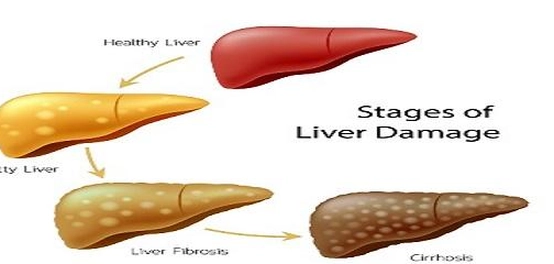

المراحل المبكرة لتليف الكبد: الأعراض الخفية

تتنوع أعراض تليف الكبد باختلاف شدة المرض ومرحلة تطوره. في كثير من الأحيان، لا تظهر أي أعراض واضحة في المراحل الأولية، خاصةً عندما تتمكن خلايا الكبد السليمة من القيام بوظائفها بشكل كافٍ. لكن قد تظهر بعض الأعراض العامة غير المحددة، والتي قد تشير إلى مشاكل صحية أخرى أيضًا. من هذه الأعراض:

تطور المرض: الأعراض الخطيرة ومضاعفاته

مع تطور تليف الكبد وتزايد تلف أنسجة الكبد، يفقد الكبد قدرته على أداء وظائفه بشكل طبيعي، مما يؤدي إلى تراكم السموم في الجسم ونقص المواد المهمة التي ينتجها الكبد. في هذه المرحلة، تظهر أعراض خطيرة ومضاعفات تهدد الحياة: